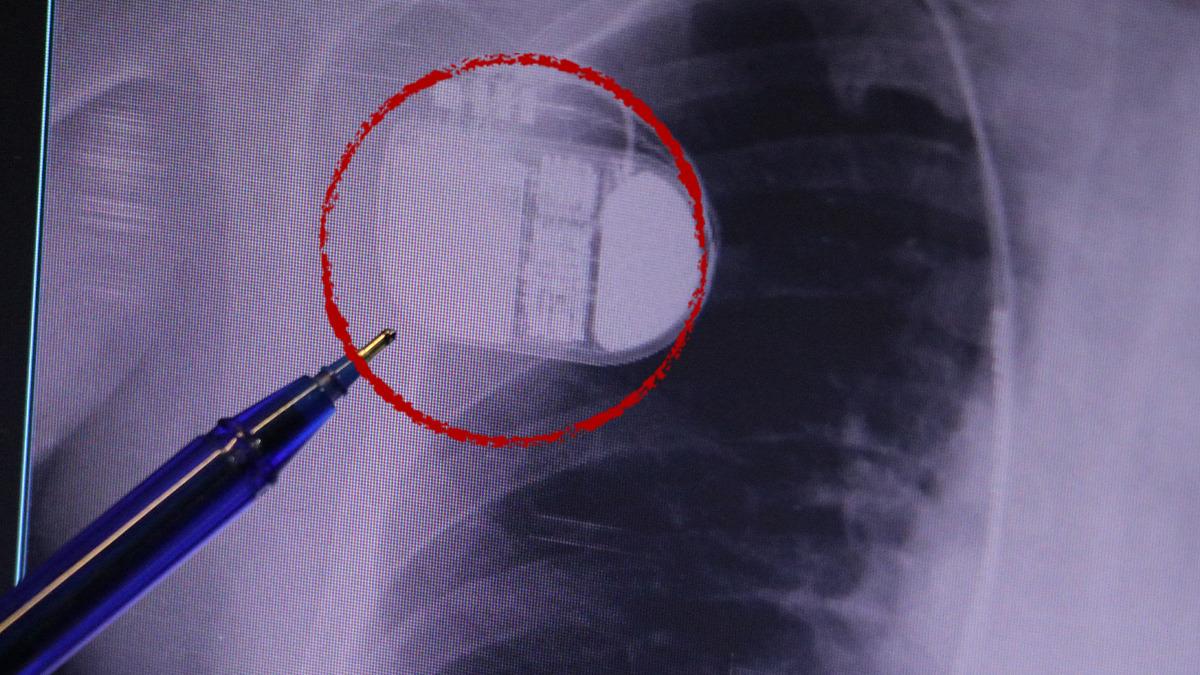

Konuyla ilgili açıklama yapan Kardiyoloji Anabilim Dalı Uzmanı Dr. İsmail Erdoğu, kalp pilinin önemine dikkat çekti. Yeni nesil kalp pillerinin MR cihazlarına erişim sağladığını ancak tarama cihazlarından geçmenin tavsiye edilmediğini söyleyen Erdoğu, şöyle konuştu: “Soğuktan kaynaklanan titreme, kalp pilinin kalbin durduğunu düşünmesine ve sahte şoka neden olabilir. Bu nedenle hastalarımıza bu dönemlerde daha dikkatli olmalarını öneriyoruz.”

MR makinesine kalp pili takılmasının mümkün olduğunu belirten Erdoğu, şöyle konuştu: “Çok büyük bir ameliyat değil ama yine de ciddi bir cerrahi işlem. Kalp pili tıpta son 30 yılın en büyük gelişmesi. Aslında bilgisayarın minyatürleştirilmiş hali olup insan vücuduna yerleştirilen bir tedavi. İnsan ömrünü önemli ölçüde uzatan bir tedavi. İnsanlar şokla hayata tutunurken, pil olmasaydı öleceğini düşündüğümüz çok sayıda hastamız var. Bu özelliğimiz Kalp pili uygun hastalarda ani ölümü önler, ritmi düzeltecek sağlık uzmanı ya da defibrilatör yoksa hastayı hayatta tutmak mümkün değildir. Hastalarımız “kalp pilim var” dediğinde hastalıktan kurtulurlar. Örneğin mikser kullanmak ya da kolu sallayacak herhangi bir hareket kalp pilini olumsuz etkileyebilir. Soğuk havalarda vücutta meydana gelen şiddetli titremeler kalp pilinin hafızasını karıştırıp gereksiz şoklara neden olabilir.